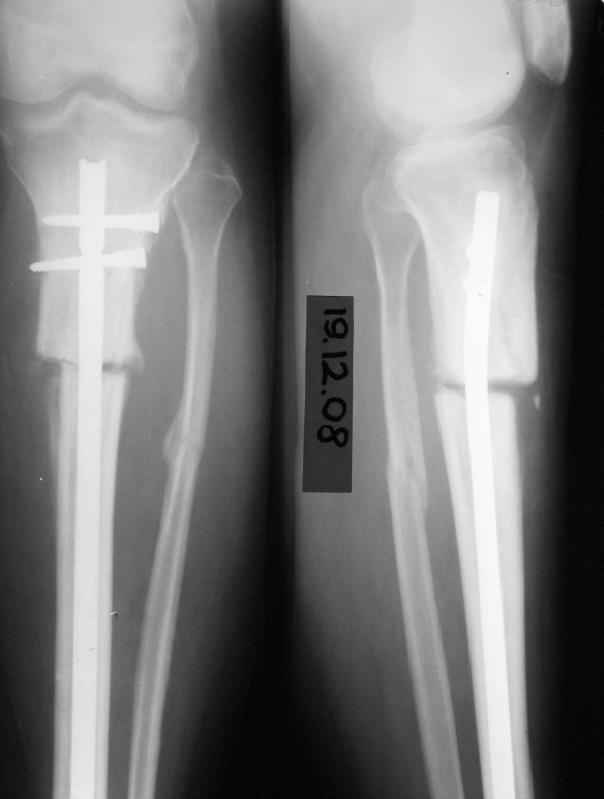

История следующая: женщина (медработник)сбита машиной 7.06.08 - о.перелом обоих костей голени в/3 со смещением. В ПДО ПХО раны,вытяжение за пяточную кость. После заживления раны 20.06.08 выполнен остеосинтез блокирующем стержнем. в течение первого месяца после травмы сохранялась субфебрильная температура на фоне приема антибиотиков. Затем температура стабилизировалась.Б-ая как положено ходила в гипсе на костылях. На контрольных рентгенограммах консолидация не достигалась, иммобилизация продлевалась. Пациентка на себе опробовала все препараты костной регенерации. В марте удален один из фиксирующих винтов. На сегодняшний день идет 11 мес. после травмы. Решается вопрос о инвалидности. Буду благодарен за предложения по дальнейшему ведению больной. Операция?

И наконец, судя по снимкам - гвоздь SIGN, или я ошибаюсь? У нас есть опыт их применения при похожих переломах (8-10 случаев) - все срастались не менее 7-8 месяцев, часто требовали динамизации и пр.

На рентгенограмме несоответствия кортикальной аппозиции в виде потерянного сегмента и пластическая деформация малоберцовой, это знак оставленного ротационного смещения во время операции.

Движение вокруг проксимального гвоздя означает разгибательно-сгибательную нестабильность в проксимальной части большеберцой.

Блокировка шурупов, которая сделана с наружной стороны с большим риском для малоберцовой, не создает двойную кортикальную стабильность. Для облегчения нахождения отверстия без рентгена, входящее кортикальное отверстие делается большего диаметра и проведенный шуруп держится только за дальний кортекс.